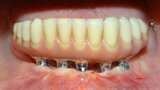

Fig. 4 Prótesis Híbrida inmediata y radiografía control con 6 años post-operatorio